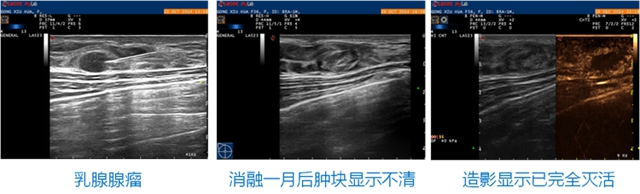

乳腺结节激光消融 已有不少国内外杂志文献和临床实践明确了激光消融对于乳腺肿瘤有极佳的临床疗效;对于<1 .5cm的恶性肿瘤,均获得彻底消融,而对于1.5—2cm以及>2cm的恶性肿瘤,完全消融率为88%和67%,对于较大的乳腺恶性肿瘤,宜采用多针联合消融为佳。而对于乳腺良性肿瘤的激光消融,同样已经受到学者关注获得了良好的临床效果。